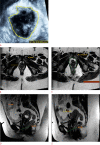

Purpose: The purpose of this study was to investigate magnetic resonance imaging (MRI) and 3-dimensional transperineal ultrasound (3D-TPUS) features of pelvic floor dysfunction (PFD) in symptomatic women in correlation with digital palpation and to define cut-offs for hiatal dimensions predictive of muscle dysfunction.

Methods: This prospective study included 73 women with symptoms suggesting PFD. 3D-TPUS, MRI, and digital palpation of the levator ani muscle were performed in all patients. Levator hiatal antero-posterior (LHap) diameter and area (LH area) were measured at rest and at maximum muscle contraction.

Results: The reduction in LHap diameter and LH area during contraction was significantly less in women with underactive pelvic floor muscle contraction (UpfmC) than in those who had normal pelvic floor muscle contraction by digital palpation (P<0.001). Statistically significant positive correlations (P<0.001) were found between the Modified Oxford Score and 3D-TPUS and MRI regarding the reduction in the LHap diameter (r=0.80 and r=0.82, respectively) and LH area (r=0.60 and r=0.70, respectively). A reduction in LHap of <6.5% on 3D-TPUS and <7.6% on MRI predicted UpfmC with sensitivities of 46.2% and 82.7%, respectively. A reduction in LH area of <3.4% on 3D-TPUS and <3.8% on MRI predicted UpfmC with sensitivities of 75.0% and 88.5%, respectively. MRI was more sensitive in detecting levator avulsion (63.4%) than 3D-TPUS (27.1%).